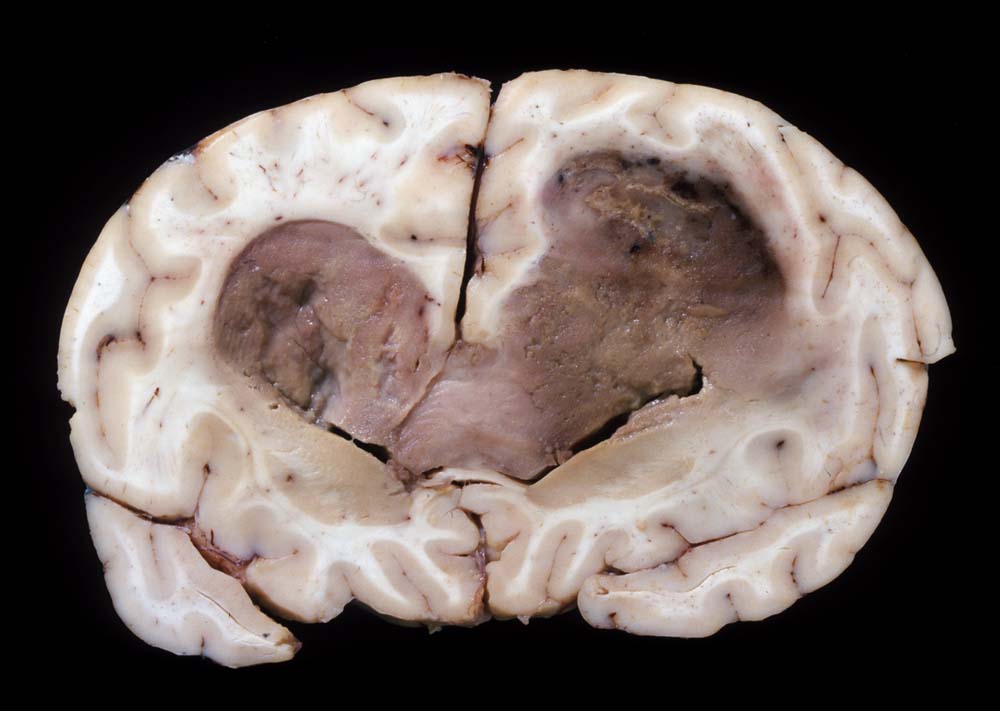

Morphologie:

Die Schnittfläche ist auffallend bunt. Dies ist bedingt durch ein Nebeneinander von graurotem vitalem Tumorgewebe, gelben Nekrosen, roten Einblutungen und gelegentlich grünlichen Gallertzysten.

Das MRI mit Kontrastmittel ist die radiologische Untersuchungsmethode der Wahl. Im CT zeigt sich eine zentrale dunkle Nekrosezone umgeben von einer ringförmigen Kontrastmittelanreicherung entsprechend der stark vaskularisierten vitalen Peripherie des Tumors. Der Ring zeigt aber nicht die Grenze des Tumors an. Tumorzellen findet man auch noch bis zu 2cm ausserhalb dieser Zone.